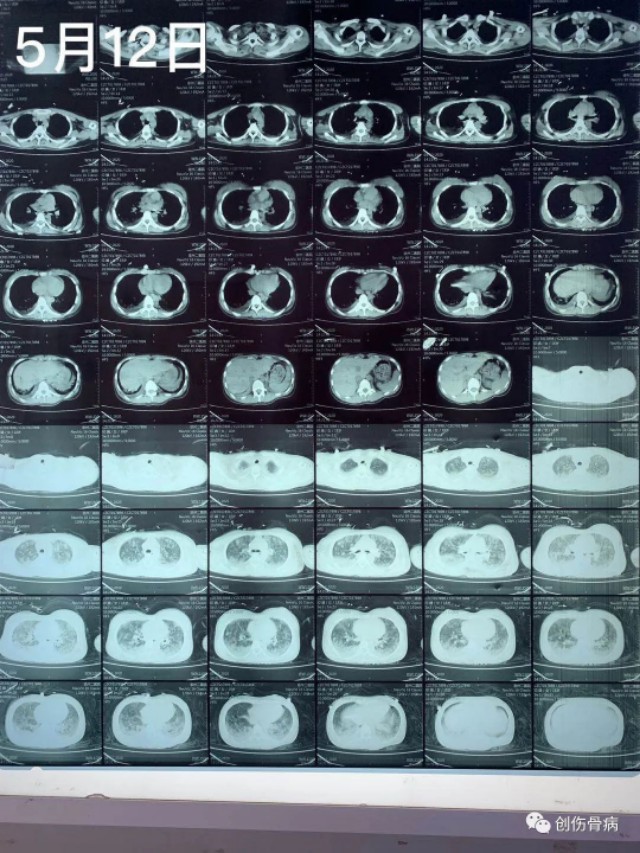

都说车祸无情,但是创伤后的并发症也依旧无情。2020年5月9日21时55分我科室接收一名18岁外伤小妹妹,当天晚上小妹妹跟爸爸妈妈路边散步被一汽车撞倒受伤,送至我院时就是一单纯右胫腓骨下段粉碎性骨折伴头皮裂伤,入院行右小腿DR及胸部CT示:2020年5月12日14时左右,小妹妹突然出现呼吸困难、烦躁不安,氧饱和度40-50%,家属诉小女孩昨日夜间有偷偷咳嗽的表现,当班医生一看就考虑脂肪栓塞立即给与安排行胸部CT示:

2020年5月12日14时左右,小妹妹突然出现呼吸困难、烦躁不安,氧饱和度40-50%,家属诉小女孩昨日夜间有偷偷咳嗽的表现,当班医生一看就考虑脂肪栓塞立即给与安排行胸部CT示:随后转入ICU气管插管、呼吸机控制呼吸、激素冲击、抗炎、脑康复等抢救治疗,短时间内出现急性肺水肿,气管插管内全是粉红色泡沫痰,恰逢月经期,各种用药都存在矛盾,血色素也直线下降,对于此类病人外界压力也挺大的,有说希望渺茫的,有说必死无疑的,也有建议转院治疗的。。。。。好在家属比较理解也比较信任我们,给予对症抢救治疗4天、13天后复查胸部CT示: